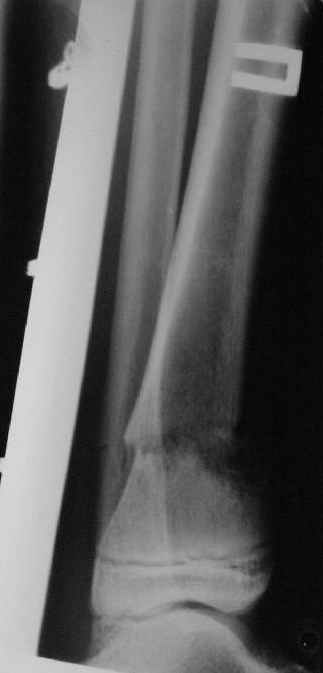

Уважаемые коллеги!Поступила пациентка 40лет, псевдоартроз Н/3 большеберцовой кости, оперирована 1,5-а года назад по поводу перелома ПИЛОНА в Австрии, травма горнолыжная.

после остеосиннтеза |  05.07.04 |  12.04.05 | Пластина удалена через 4-е месяца (миграция винтов), полимерная повязка на 2-а мес. Беспокоит деформация голени,укорочение 1-1,5см, боли незначительные, движения в г/стопном суставе в полном объёме, ходит с полной нагрузкой на ногу, подвижность в переломе не определяется. Одномоментное исправление деформации, костная пластика (chronOS)+ пластина? Аппаратная коррекция, затем пластина? Аппарат? Прошу Ваших советов. С Уважением А.Миронов